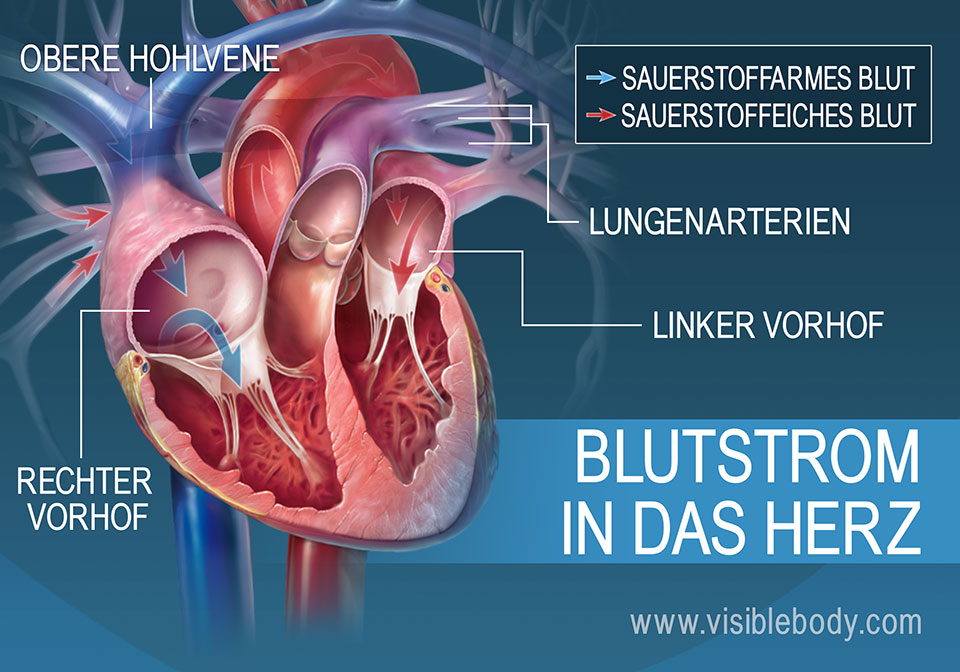

Die Pumpleistung ist die Menge des Blutes, die das Herz innerhalb einer bestimmten Zeit in den Blutkreislauf pumpt. Das gesunde Herz eines erwachsenen Menschen pumpt in Ruhe etwa 5 bis 6 Liter pro Minute. Bei einer körperlichen Belastung steigt dieses Herzminutenvolumen auf 20 bis 25 Liter. Krankheiten können die Pumpleistung des Herzens unnatürlich senken oder steigern.. In jeder Minute wird so einmal die gesamte Blutmenge – beim Erwachsenen fünf bis sechs Liter – durch den Körper befördert. Doch wie schafft das Herz jeden Tag diese Schwerstarbeit und wie funktioniert diese menschliche Pumpe? Herz-Kreislauf-System: So fließt das Blut. Das Herz ist das Zentrum des Blutkreislaufs.

Das Herzzeitvolumen (HZV, englisch cardiac output CO) ist das Volumen des Blutes, das pro Zeitspanne vom Herzen gepumpt wird (Volumenstrom).Die übliche Maßeinheit in der Humanmedizin ist Liter pro Minute, wobei dann vom Herzminutenvolumen (HMV), früher auch Minutenvolumen des Herzens, gesprochen wird.. Das Herzzeitvolumen ist ein Maß für die Pumpleistung des Herzens bezüglich der.. Der venöse Rückstrom zum Herzen bestimmt ganz wesentlich, wie viel Blut das Herz jede Minute auswirft. Abhängig von diesem Rückfluss pumpt das Herz automatisch das zurückströmende Blut in den Körperkreislauf. Je mehr Blut zurückströmt, desto mehr Blut wird vom Herzen ausgeworfen und umgekehrt.